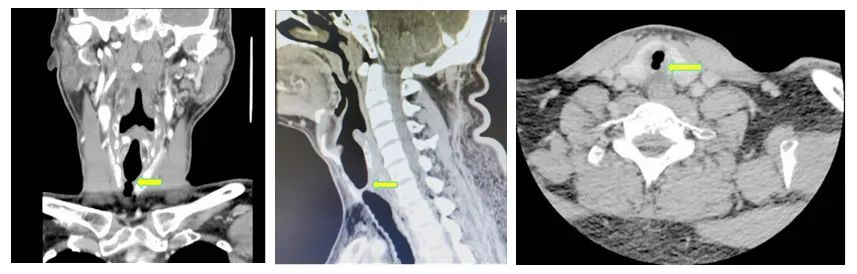

▲颈部CT提示气管狭窄

患者男性,42岁,不久前因脓毒症、心源性休克在外院行气插管、呼吸机辅助呼吸等治疗,经治疗,病情相对好转、稳定,但仍有明显呼吸困难,后于2月14日收治我院心血管内科。行支气管镜见声门下气管瘢痕组织增生,呈漏斗状、蹼样狭窄,最窄处直径约3mm×4mm。我院呼吸与危重症医学科带头人罗少华会诊后认为:该患者气管明显狭窄,有呼吸困难症状,且存在痰堵窒息风险,建议行呼吸介入治疗。